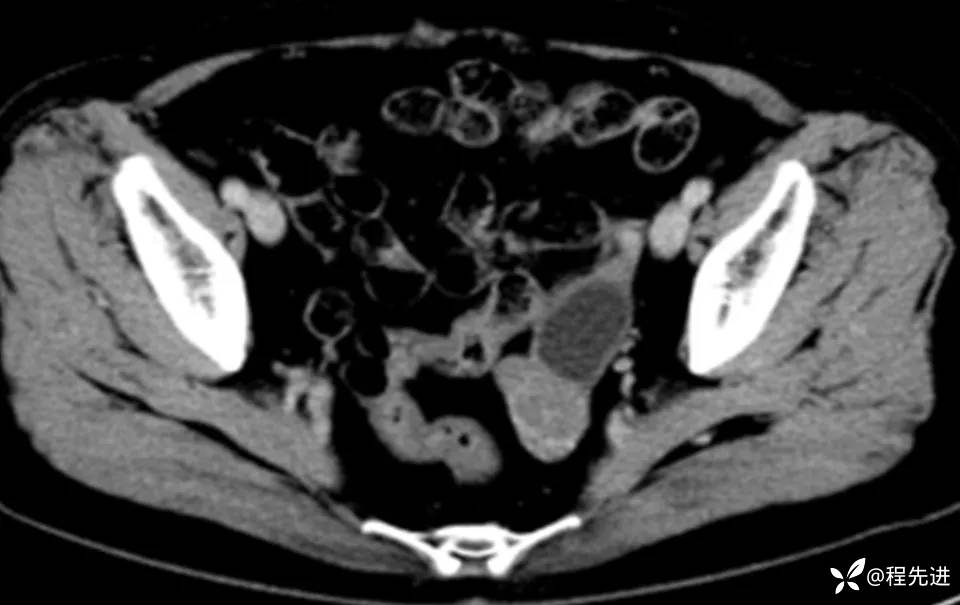

CT平扫+增强:

img